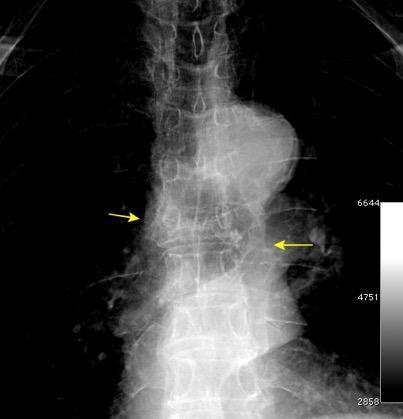

Líneas paraespinales formando un “paréntesis” por encima del diafragma. El signo señala el origen “intratorácico” de la lesión.

Conrad A et al. Pott’s disease associated with large and multiple abscesses in a 30-year-old migrant from Chad. BMJ Case Rep 2018

(lesiones toracoabdominales) La divergencia de las líneas paraespinales apunta a lesión toracoabdominal, que desde el tórax desciende y penetra en el abdomen.

Signo del “iceberg” positivo en Tb vertebral

Afectación por vía hematógena. Región dorsolumbar más frecuente. Afectación inicial: irregularidad de los platillos vertebrales, disminución del disco intervertebral con esclerosis ósea adyacente. Kim. Radiographics.2001